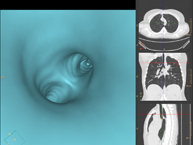

- Virtual colonoscopy

Virtual colonoscopy is a non-invasive technique that allows three-dimensional and two-dimensional visualisation of the large intestine or colon by taking sequential images captured with a state-of-the-art MDCT scanner. The quality of the images allows virtual navigation through the rectum and colon thanks to processing on specialised workstations. Preparation for the test consists of following a low-fibre diet for three days before the test (to cleanse the colon and rectum) and ingesting an iodinated oral contrast agent the day before the test (to mark the stool so that it can be correctly distinguished from any colonic lesions). Unlike fibrocolonoscopy, no sedation or bowel preparation is required. The test is performed in the CT room, where air is blown through a small flexible tube to distend the colon.